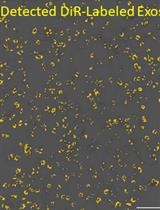

3. ExoView R200 platform (Software, ExoViewer 2.5.0)

Graphical overview of extracellular vesicle (EV) isolation from plasma samples. (A) Flowchart of the isolation of extracellular vesicles from plasma, detailing plasma preparation and EV purification. (B) Transmission electron microscopy (TEM) image of EVs isolated from human plasma samples. Scale bar, 100 nm.